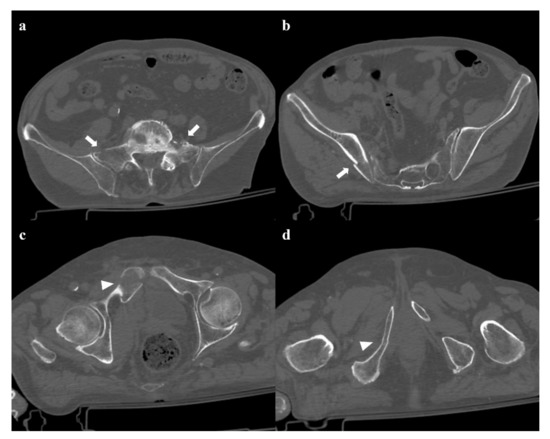

17 pages, 55736 KB

Imaging Review of Pelvic Ring Fractures and Its Complications in High-Energy Trauma

by Edoardo Leone, Andrea Garipoli, Umberto Ripani, Riccardo Maria Lanzetti, Marco Spoliti, Domenico Creta, Carolina Giannace, Antonio Galluzzo, Margherita Trinci and Michele Galluzzo

Pelvic ring fractures are common in high-energy blunt trauma, especially in traffic accidents. These types of injuries have a high rate of morbidity and mortality, due to the common instability of the fractures, and the associated intrapelvic vascular and visceral complications. Computed tomography [...] Read more.

Pelvic ring fractures are common in high-energy blunt trauma, especially in traffic accidents. These types of injuries have a high rate of morbidity and mortality, due to the common instability of the fractures, and the associated intrapelvic vascular and visceral complications. Computed tomography (CT) is the gold standard technique in the evaluation of pelvic trauma because it can quickly and accurately identify pelvic ring fractures, intrapelvic active bleeding, and lesions of other body systems. To properly guide the multidisciplinary management of the polytrauma patient, a classification criterion is mandatory. In this review, we decided to focus on the Young and Burgess classification, because it combines the mechanism and the stability of the fractures, helping to accurately identify injuries and related complications. Full article